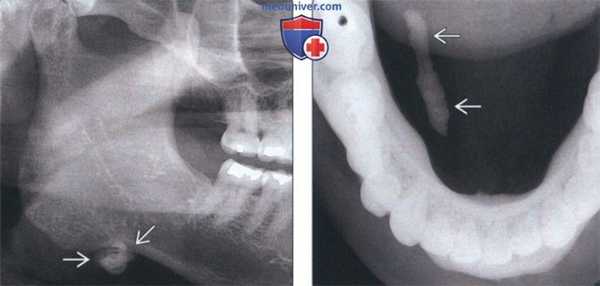

(Слева) На кадрированной панорамной рентгенограмме определяется сиалолит правой поднижнечелюстной железы, находящийся возле ее нижнего края. Накладывала на нижнюю челюсть, поднижнечелюстные сиалолиты могут имитировать очаговый идиопатический остеосклероз.

(Справа) На окклюзионной рентгенограмме правой половины нижней челюсти определяется вытянутый сиалолит в вартоновом протоке поднижнечелюстной железы. Тридцать процентов поднижнечелюстных сиалолитов возникают в области ворот или в проксимальных отделах вартонова протока.

2. Рентгенография при поднижнечелюстном сиалолите:

• Интраоральная и панорамная рентгенография, сиалография:

о Округлый, овальный или вытянутый рентгеноконтрастный участок; ± слоистая структура

о Рентгенонегативный участок или дефект наполнения при традиционной сиалографии

о Традиционная сиалография: расширенные участки, перемежающиеся со стриктурами протока (вследствие инфекции)